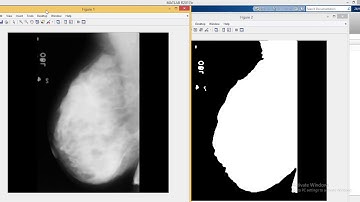

Breast Cancer Detection in Mammograms Using Matlab